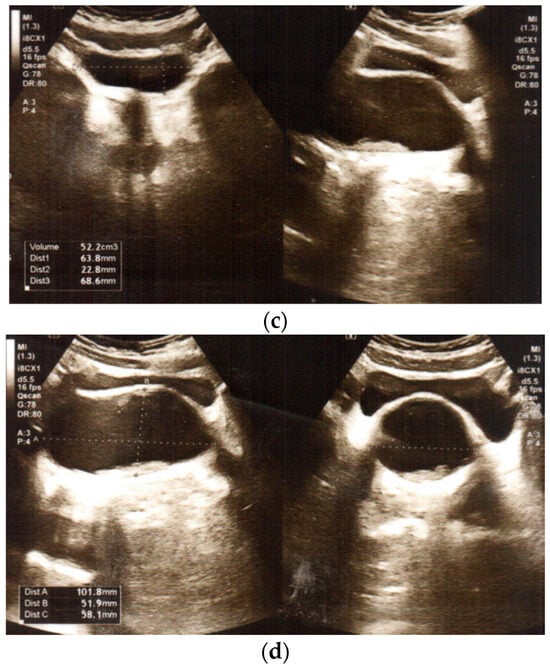

We present the medical history of a 16.5-year-old girl who underwent urgent surgery at the age of 12 years. The girl was admitted to the Department of Urology due to complaints of severe abdominal pain on the sixth day of menstruation, with bladder pressure. There was no reaction to analgetic or spasmolytic medications. Transabdominal pelvic ultrasound examination revealed duplication of the uterus (uterus with right-sided oval hypoechogenic structure) and vagina, with a right vagina of 52 mm × 58 mm × 10 mm filled with blood (haematocolpos), normal ovaries (Figure 1). Abdominal ultrasound showed right renal agenesis with normal left kidney and ureter, and constricted bladder.

Figure 1.

Transabdominal pelvic ultrasound at the time of diagnosis: (a,b) duplication of uterus: uterus with right-sided oval hypoechogenic structure, and normal ovaries (c,d) duplication of vagina, with haematocolpos on the right side.